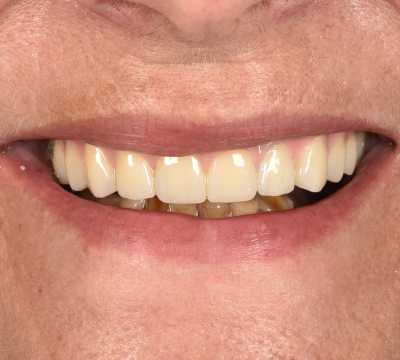

Cazul 70

All on 6, implanturi orale speciale pterigoide

Cazul 70: All on 6

Imaginile sunt prezentate în ordinea evoluției tratamentului, de la situația inițială la rezultatul final.